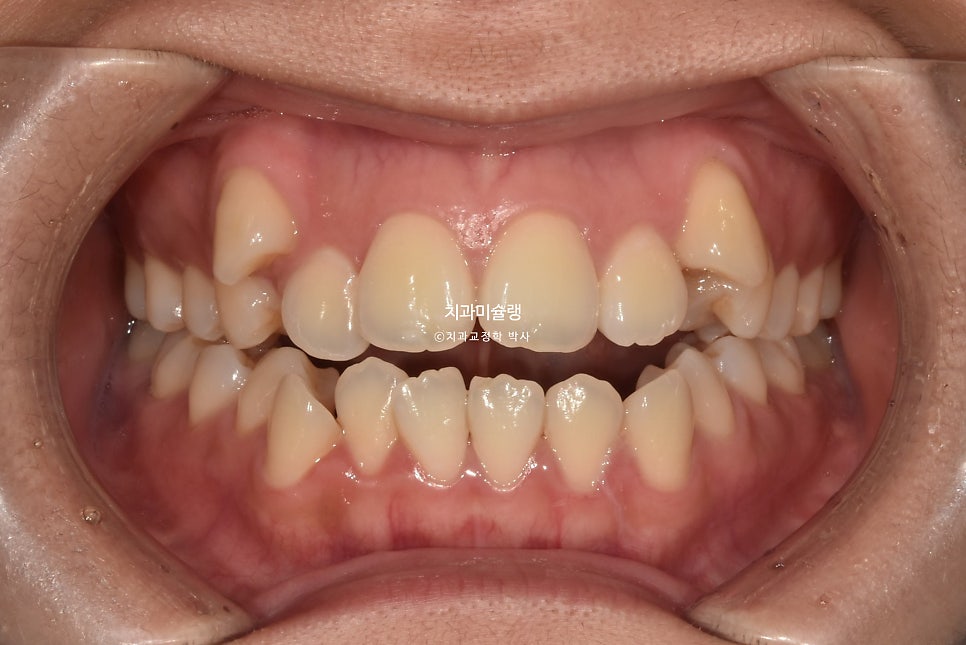

초진 시 환자 상태

2023년 9월 내원

덧니와 개방교합 때문에 오신 환자분 입니다.

덧니가 상당히 심한편입니다.

앞니뿐 아니라 작은어금니까지 또있는 개방교합입니다.

어금니 교합관계는 2급 입니다.

덧니를 제자리 시키려면 발치가 필수적인 상황입니다만

입매를 보면 하관에서 인중이 차지하는 비율이 크고 입술이 얇습니다.

저의 박사연구논문에서 밝혔듯 발치교정후 입술이 얇아지고 인중이 길어보이는 현상은 피할수 없습니다.